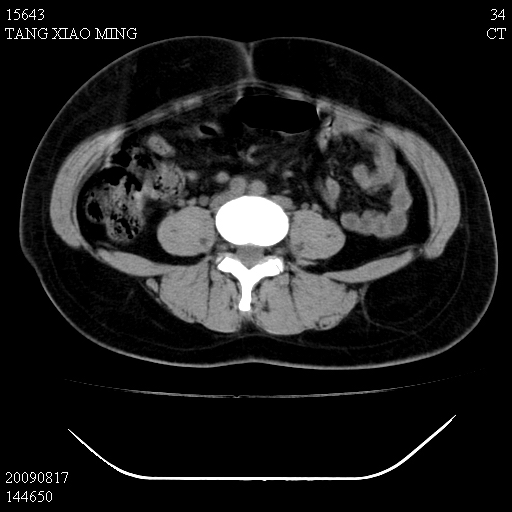

标题: CT21692:盆腔病变

女,33岁,右下腹痛2年余,既往宫外孕病史,如在我院手术,结果下周公布,

可能的诊断。1子宫内膜异位【子宫腺肌症并右卵巢巧克力囊肿】;2 右卵巢囊腺瘤。子宫肌瘤

1)考虑卵巢巧克力囊肿,不排除卵巢囊腺瘤。2)子宫肌瘤可能。

卵巢囊腺瘤,子宫肌瘤,直肠壁厚,不除外占位.